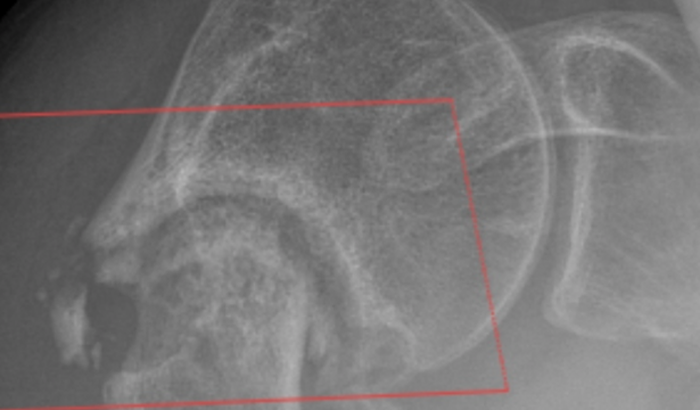

Meu namorado foi atingido por uma carro em 2020 e fraturou o úmero superior direito, fez cirurgia e colocou fios de Kirschner, fez fisioterapia mas nunca chegou a ficar 100%. Perdendo 75% da movimentação do braço! Após novo trauma no braço descobriu que a fratura nunca colou / nunca se consolidou, criando pseudoartrose, agora precisando fazer uma nova cirurgia e por uma placa, algo que não é contemplado pelo SUS / Sistema Único de Saúde. Ele não consegue trabalhar e se manter, sente dor e a movimentação está menor do que antes! O mesmo precisará entrar na justiça, sabemos como isso é demorado. Então pretendemos fazer particular. A cirurgia tem um custo estimado em 30 mil reais! Toda ajuda será bem vinda!

Cid M84.1